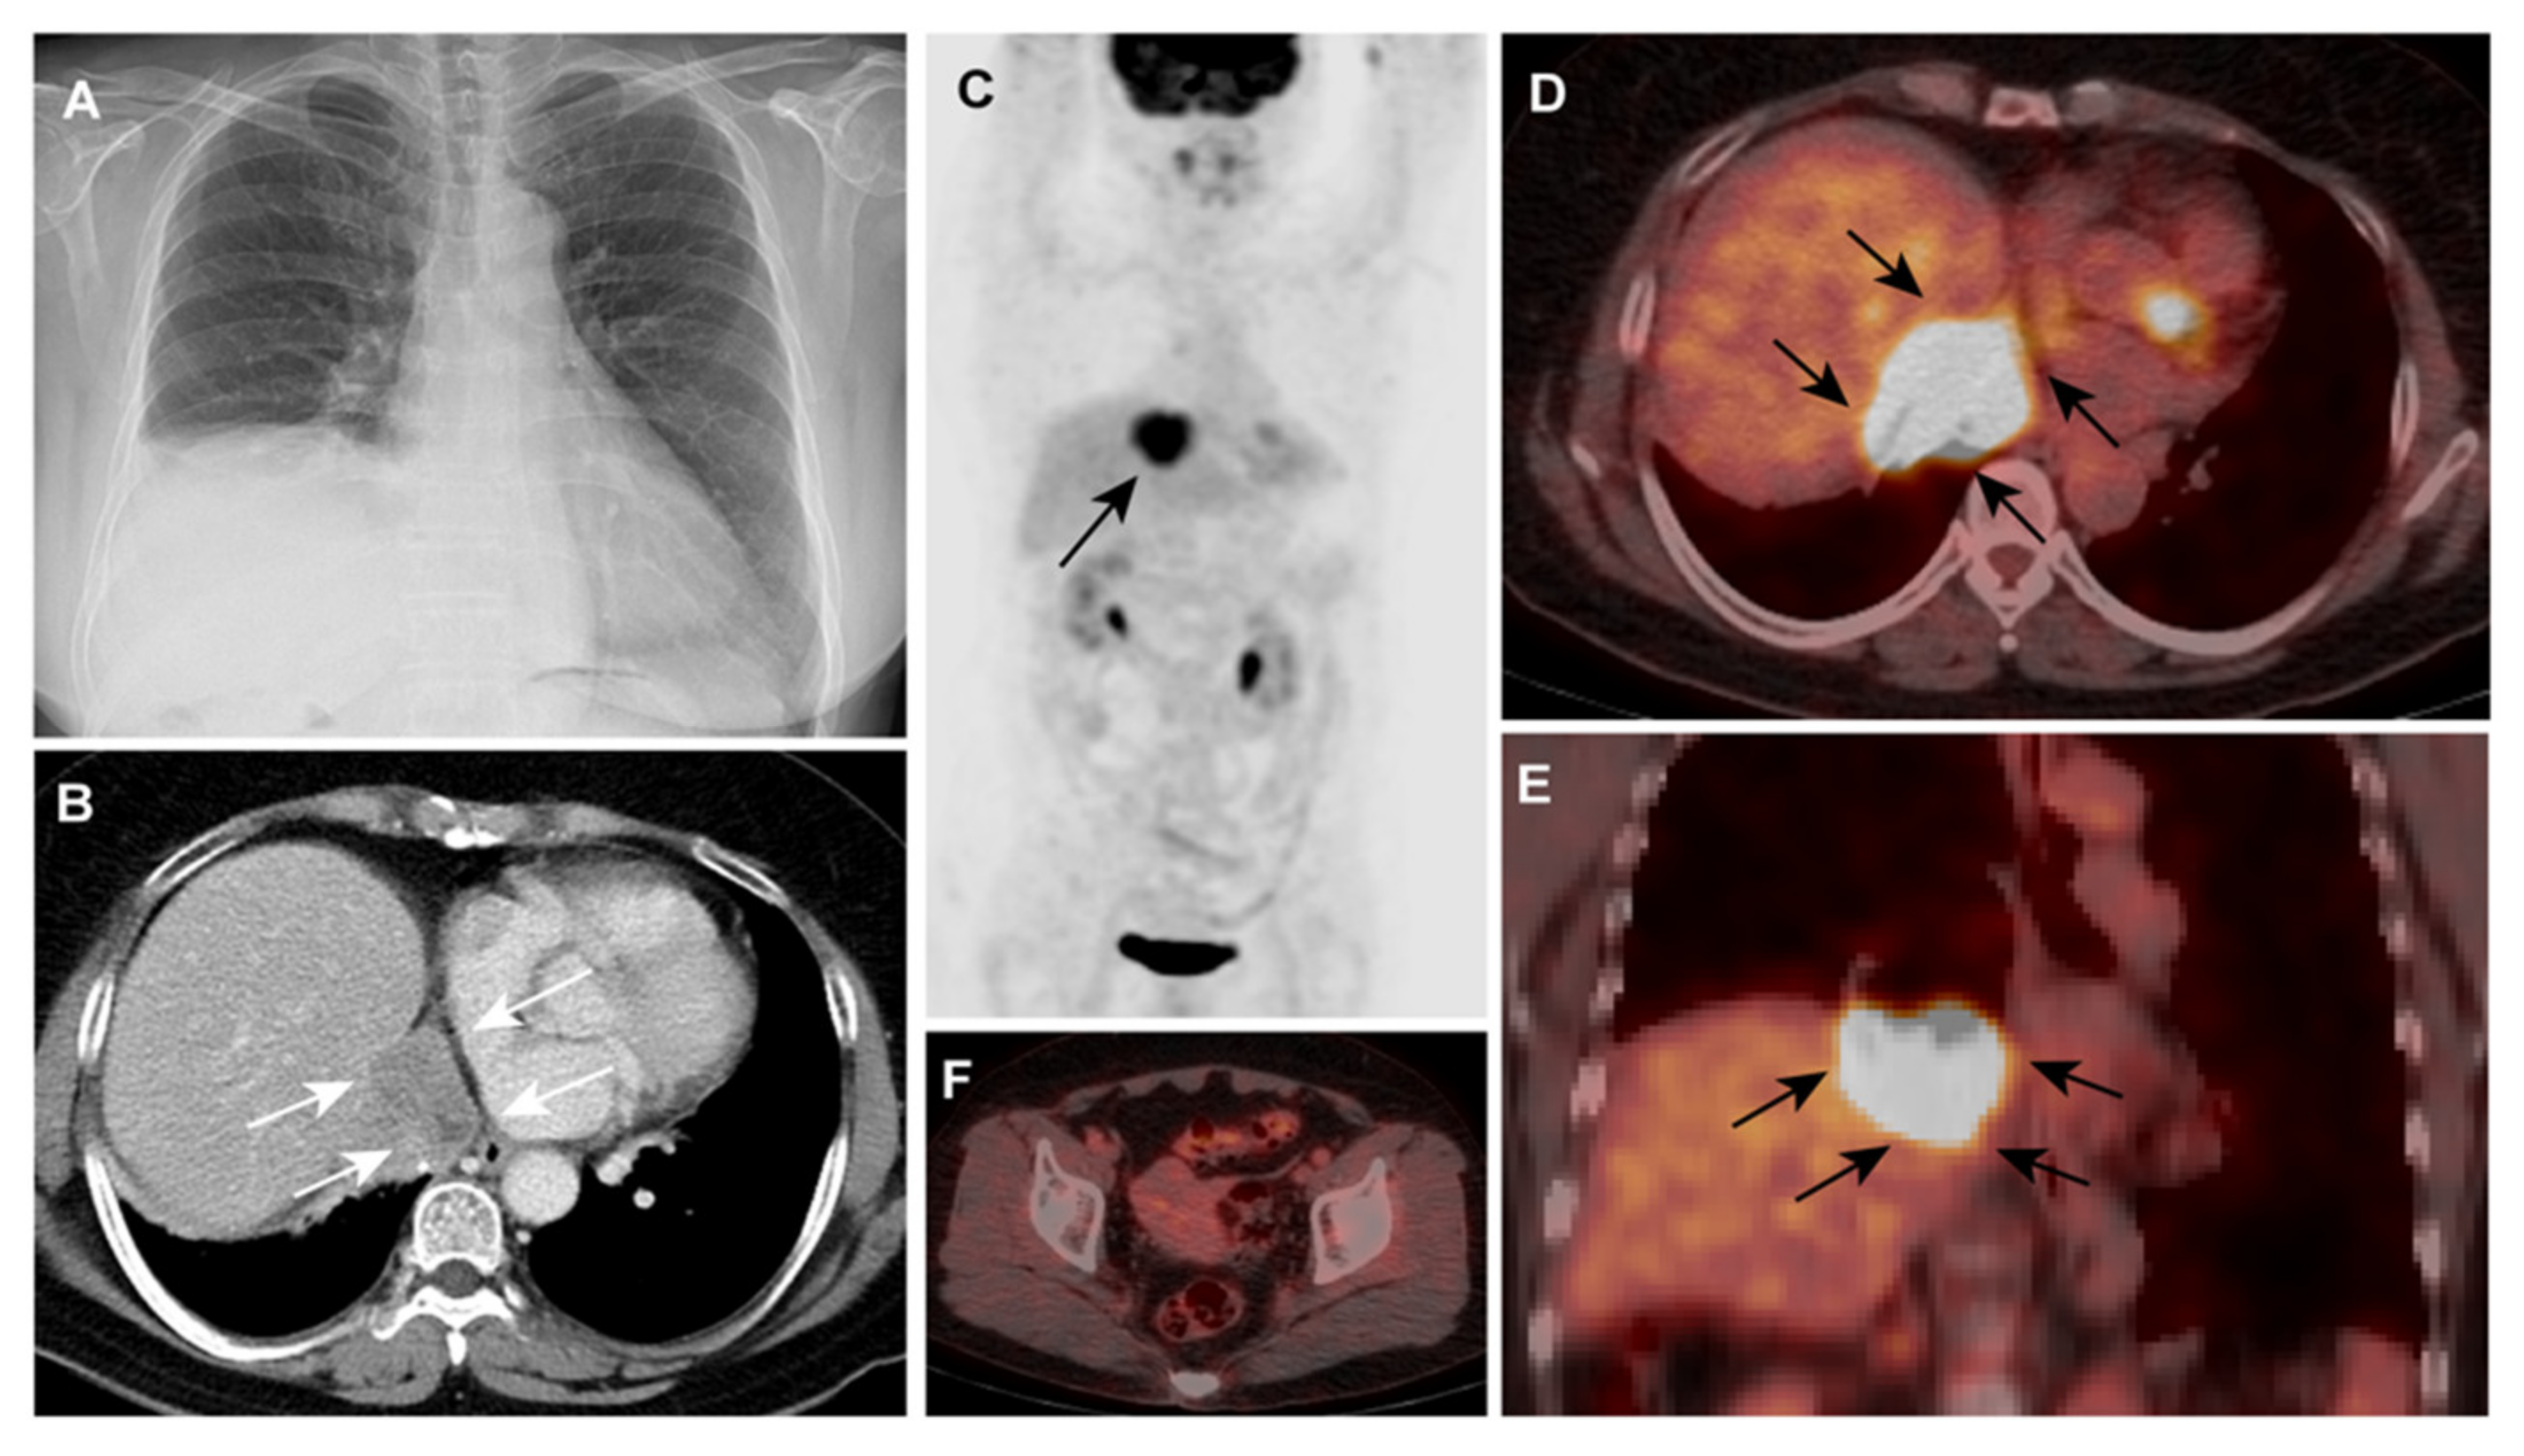

What Cancers Are Detected By Pet Scan - Asymptomatic Myocardial Metastasis From Cancers Of Upper Aero Digestive Tract Detected On Fdg Pet Ct A Series Of 4 Cases Cancer Imaging Full Text : In some instances, depending on the prostate cancer tumor type, fdg pet scans may be used for the restaging of recurrent prostate cancer as well.. Do all cancers show up on pet scan? Once you're ready to start the scan, you'll be asked to lie on your back on a platform. Doctors introduce a tracer into the system and areas with high chemical activity show up on the screen as bright spots. Pet scans can show solid tumors in the brain, prostate, thyroid, lungs, and cervix. To determine whether the cancer has spread to the lymph nodes

Pet scans can be used to: To determine whether the cancer has spread to the lymph nodes There are many different radiotracers used in pet scans that take advantage of other cellular processes. For cancer, pet is especially useful as it can scan the entire body and pinpoint both a primary tumor and areas of metastasis (where the cancer has spread). Prior to a pet scan, the patient receives an injection of a substance that contains a type of sugar attached to a radioactive isotope.

Pet/ct, which is a combination of positron emission tomography (pet) with computerized tomography (ct), is a powerful, essential tool for cancer detection and diagnosis.

The platform will enter a long tube where the pet scan is performed. Pet scans can show solid tumors in the brain, prostate, thyroid, lungs, and cervix. Pet scans can be used to: Positron emission tomography (pet) scans: Your healthcare provider may order a pet scan to check for signs of: The reality is that you cannot rely on a ct scan (or ultrasound, mri, or blood test) to tell you if you have cancer. Positron emission tomography (pet) scan. Doctors introduce a tracer into the system and areas with high chemical activity show up on the screen as bright spots. Pet/ct, which is a combination of positron emission tomography (pet) with computerized tomography (ct), is a powerful, essential tool for cancer detection and diagnosis. Before the scan, you receive an injection of a tracer called radioactive glucose. The scans can also evaluate the occurrence of colorectal, lymphoma, melanoma, and pancreatic tumors. However, as with most studies, there are a few exceptions. It is only with a pet/ct scan that you will know for sure.

Help diagnose and manage central nervous system disorders such as depression, epilepsy, alzheimer's and parkinson's disease. Because of this high level of chemical activity, cancer cells show up as bright spots on pet scans. Coronary artery disease, heart attack or other heart problems. With that being said, not all cancers can be detected by pet. A pet scan is similar to a ct scan; Pet is primarily used to diagnose cancer, cardiovascular disease, and neurologic disorders. Before the scan, you receive an injection of a tracer called radioactive glucose. Pet scans can help detect cancer and how far it has spread. The pet/ct scanner produces an image of the anatomy fused with the functional images of the use of sugar by cells. Doctors often order pet scans to stage a cancer or to assess whether treatment is working. Do all cancers show up on pet scan? The scans can also evaluate the occurrence of colorectal, lymphoma, melanoma, and pancreatic tumors. Brain disorders, such as brain tumors, epilepsy, dementia and alzheimer's disease.

Best Scans To Detect Cancer Envision Radiology from www.envrad.com Coronary artery disease, heart attack or other heart problems. Once you're ready to start the scan, you'll be asked to lie on your back on a platform. The use of pet scans may help doctors more accurately detect the presence and location of cancer cells. To determine whether the cancer has spread to the lymph nodes However, as with most studies, there are a few exceptions. However, pet scans can detect live cancer tissue. The parts of the body that need the most energy and the energy they use is sugar (also called glucose). Types of cancer detected and treated in the world of oncology, pet/ct is often used to detect breast cancer, lung cancer, stomach and pancreatic cancers, gi tumors, lymphoma, melanoma and much more.

Cancer cells have a higher metabolic rate than noncancerous cells. The pet/ct scanner produces an image of the anatomy fused with the functional images of the use of sugar by cells. Before the scan, you receive an injection of a tracer called radioactive glucose. A pet scan is similar to a ct scan; A pet scan uses a special substance, this substance is called tracker and is almost exactly like sugar, but has a small radioactive part. However, pet scans can detect live cancer tissue. Cell growth can be detected with a pet scan, but not all cancer types can be seen. Because of this high level of chemical activity, cancer cells show up as bright spots on pet scans. Information on other radiotracers and their use can be found in the molecular imaging and contrast agent database. There are many different radiotracers used in pet scans that take advantage of other cellular processes. Because cancer cells often take up more glucose than healthy cells, the pictures can be used to find cancer in the body. Pet scans usually use a form of radioactive sugar. Pet scans can be useful for evaluating people after breast cancer has already been diagnosed, in a number of different ways: